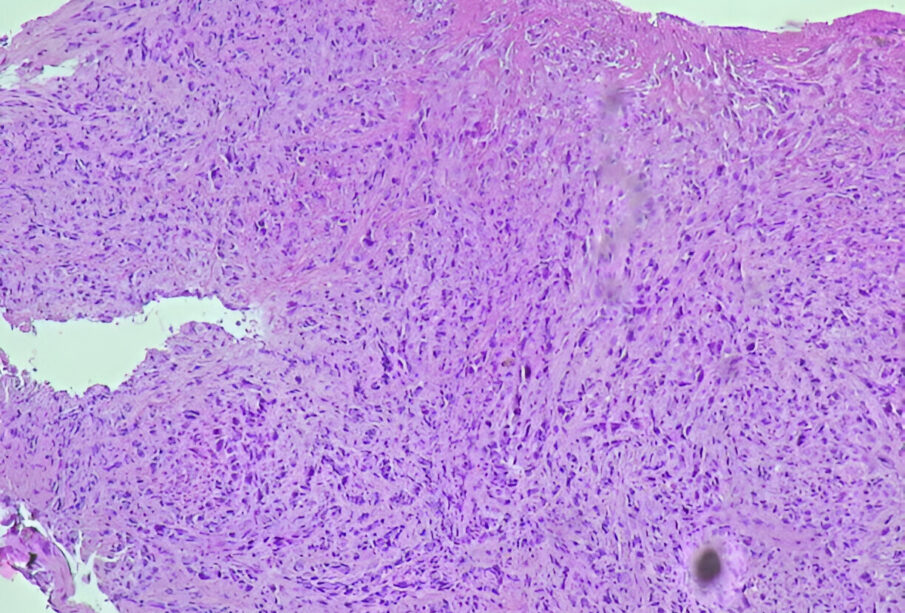

- Καλοήθης ή κακοήθης όγκος στο στομάχι ή τον οισοφάγο

Υπάρχουν αρκετές παθήσεις που μπορεί να προκαλέσουν αιματέμεση και η διαγνωστική διαδικασία ξεκινά με τη λήψη λεπτομερούς ιστορικού συμπτωμάτων και πληροφόρησης σχετικά με τυχόν πρόσφατους τραυματισμούς. Στη συνέχεια, ο γιατρός μπορεί να συστήσει απεικονιστικές εξετάσεις ώστε να διαπιστωθούν εσωτερικές ανωμαλίες, όπως τραυματισμοί οργάνων ή ύπαρξη μη φυσιολογικών μορφωμάτων. Μεταξύ των πιο συχνών απεικονιστικών μεθόδων είναι η ενδοσκόπηση ανώτερου πεπτικού συστήματος για ανίχνευση αίματος στο στομάχι. Κατά τη διαδικασία αυτή, με χρήση τοπικής αναισθησίας, ένας λεπτός και εύκαμπτος σωλήνας με κάμερα (ενδοσκόπιο) τοποθετείται μέσω του στόματος στο στομάχι, επιτρέποντας στον γιατρό να εξετάσει το εσωτερικό για τυχόν πηγή αιμορραγίας. Επίσης, μπορεί να διενεργηθεί εξέταση αίματος για εκτίμηση των επιπέδων και του όγκου του αίματος που χάθηκε. Εάν κριθεί απαραίτητο, πραγματοποιείται και βιοψία ώστε να αναγνωριστεί αν η αιμορραγία οφείλεται σε φλεγμονή, λοίμωξη ή κακοήθεια. Επιπλέον εξετάσεις μπορεί να συστηθούν βάσει των αποτελεσμάτων των πρώτων ελέγχων.